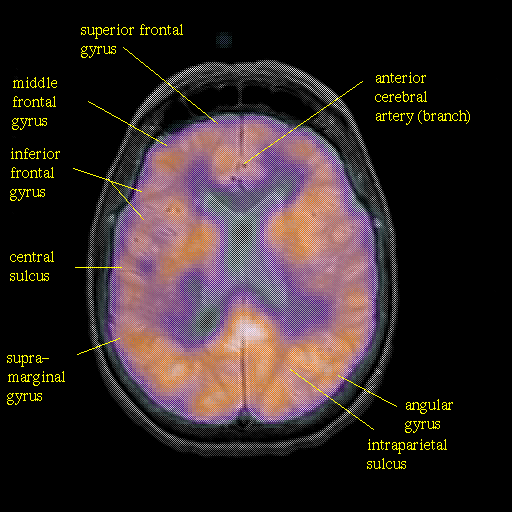

overlay : Slice 33

Slice 33

Pointers

Labeled